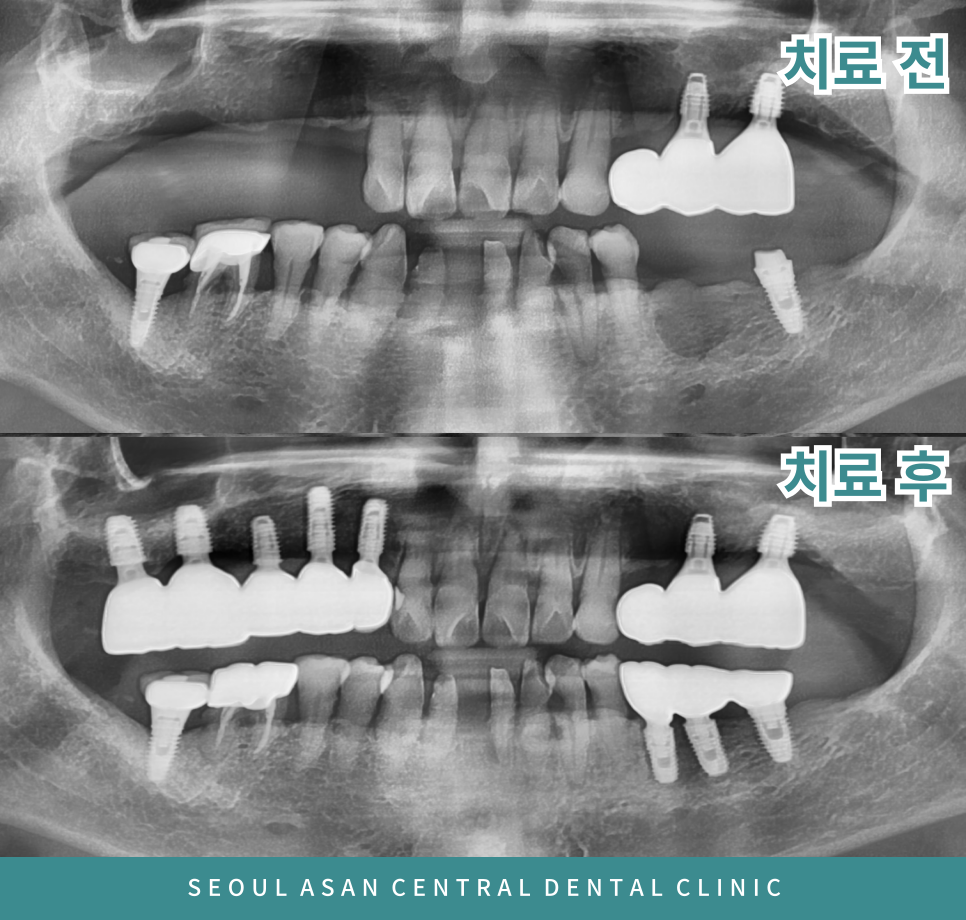

환자분께서는 위턱 오른쪽과

아래턱 왼쪽 잇몸뼈가 부족하여

임플란트가 어려워 성남치과

의료진과 충분한 상담을 통해

치료방법을 결정해야 하는데요.

위턱 오른쪽 어금니 부위는

상악동이 내려와 있어

임플란트 식립을 위해서는

상악동 거상술이 필요하고

사진상에서 까맣게 보이는 것처럼

뼈가 많이 녹아 약해져 있다면

뼈이식을 동반하여

임플란트 식립이 필요할 수 있습니다.

성남치과, 성공적인 뼈 이식과

임플란트 식립을 위해

3D CT 촬영을 통해 개개인의 잇몸뼈 상태와

구강상태를 정밀하게 파악한 후

충분한 상담후에 진행되어야 합니다.

위 아래 모두 임플란트와 잇몸뼈가

단단히 유착될 수 있도록 충분히 기다린 후

최종 보철물을 올려 마무리 되어야합니다.